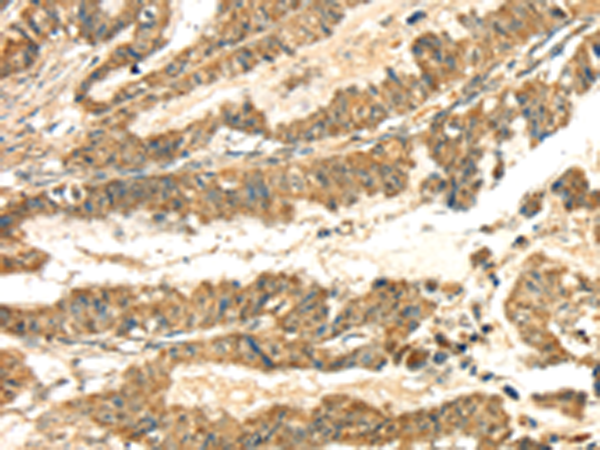

分类: 科研抗体货号: P08772别名: CTLN2; CITRIN; ARALAR2应用: WB,IHC反应种属: Human, Mouse